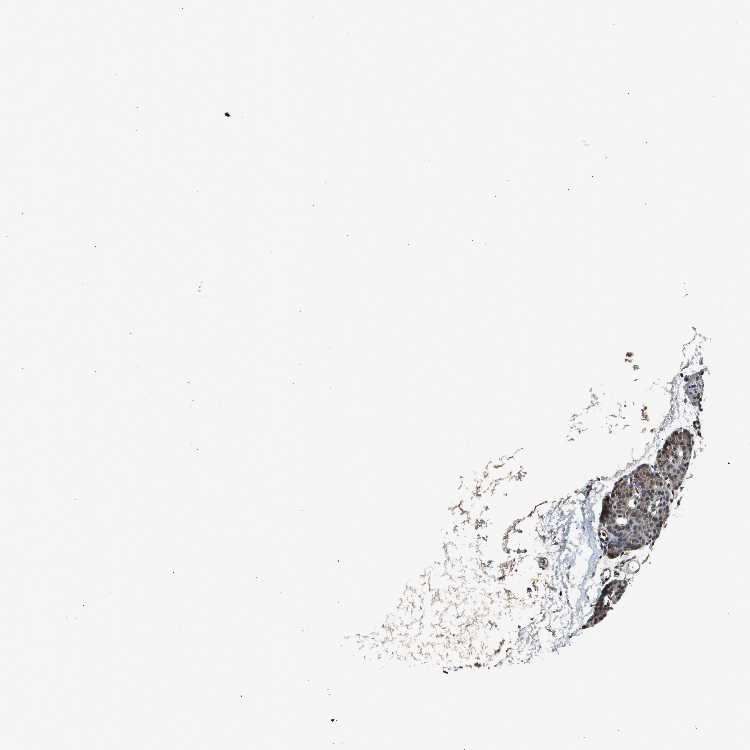

PARATHYROID GLAND - Antibody stainingi

Antibody staining in the annotated cell types in the current human tissue is reported as not detected, low, medium, or high, based on conventional immunohistochemistry profiling in selected tissues. This score is based on the combination of the staining intensity and fraction of stained cells.

Each image is clickable and will lead to virtual microscopy that enables deeper exploration of all samples and also displays staining intensity scores, fraction scores and subcellular localization as well as patient and tissue information for each sample.

Antibody HPA006872

Glandular cells High